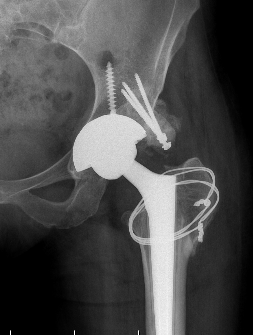

Crowe I

Crowe II

Crowe III

Crowe IV

Crowe II / III: Medialize cup, superolateral femoral head augment, trochanteric slide